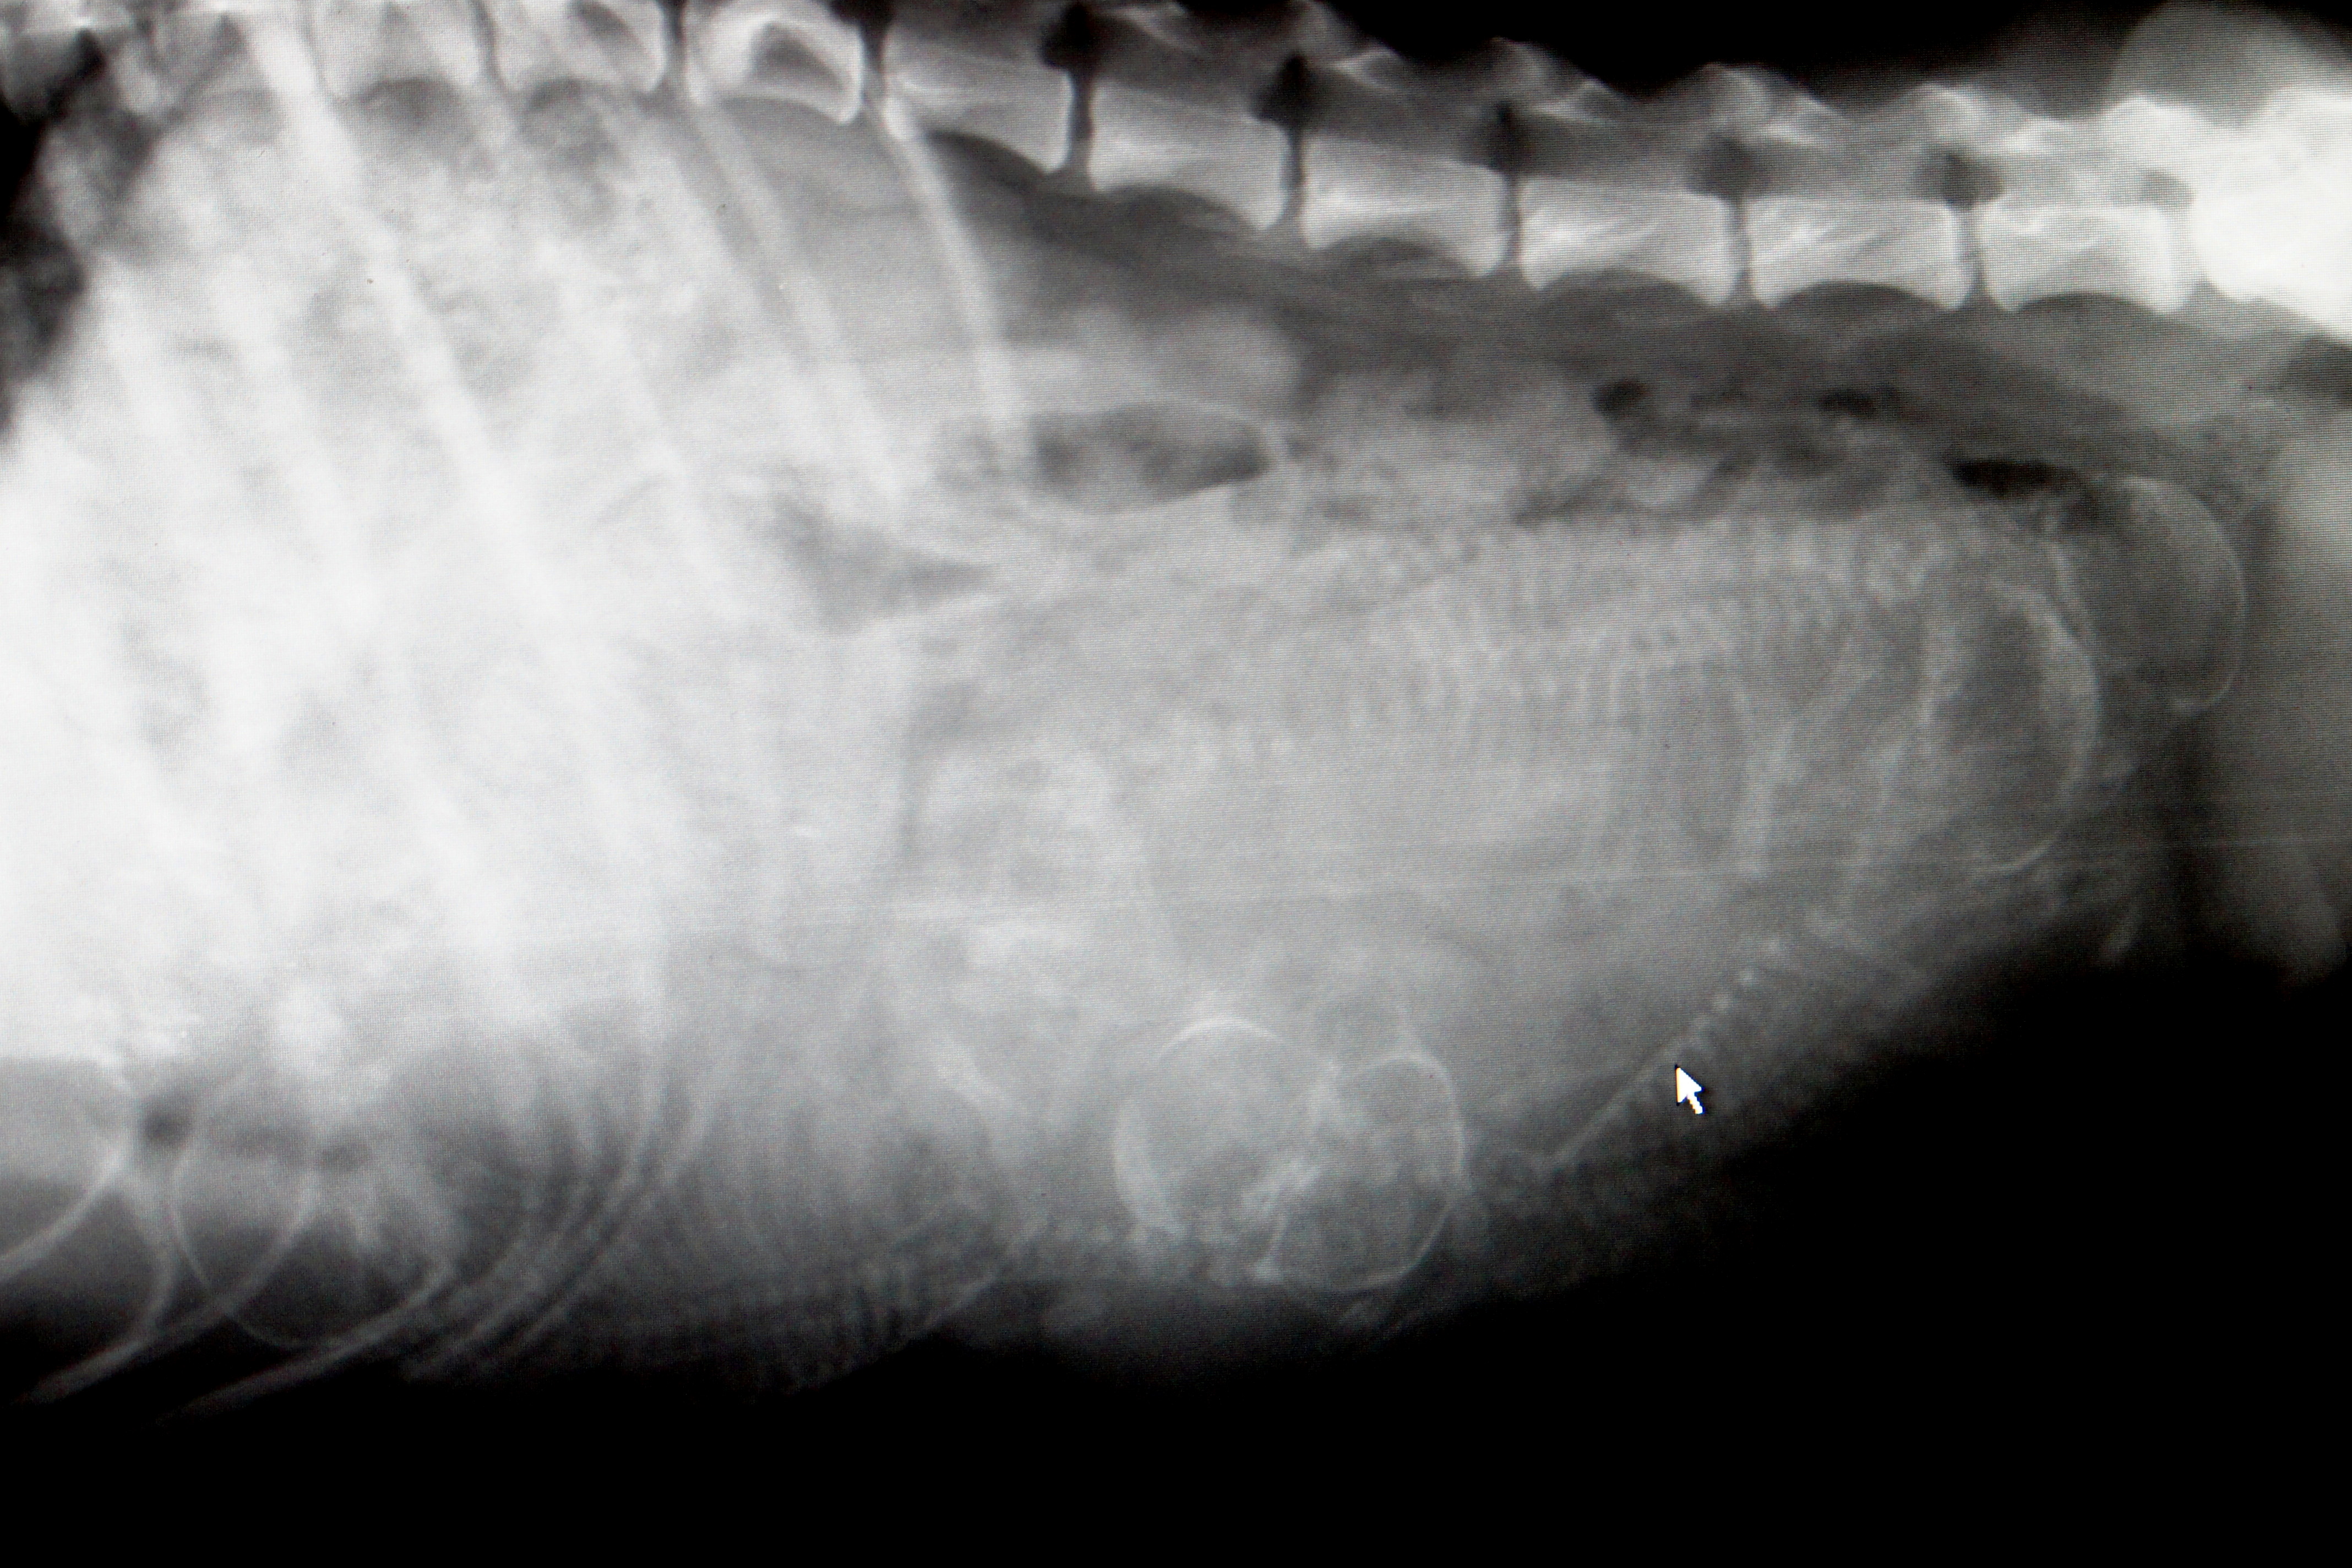

På torsdag 7. mai var Sara til rtg for å se hvor mange valper det er.

Bilde jeg tok av rtg bilde ble ikke så bra, men hos veterinæren var det lett å se. Så nå gjenstår det å se hva det blir. 🙂